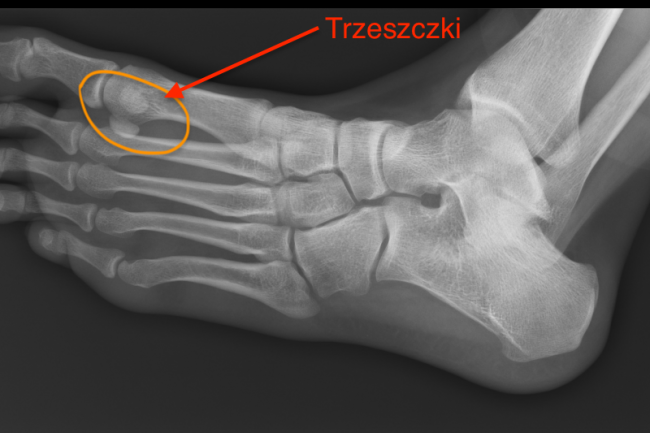

Details